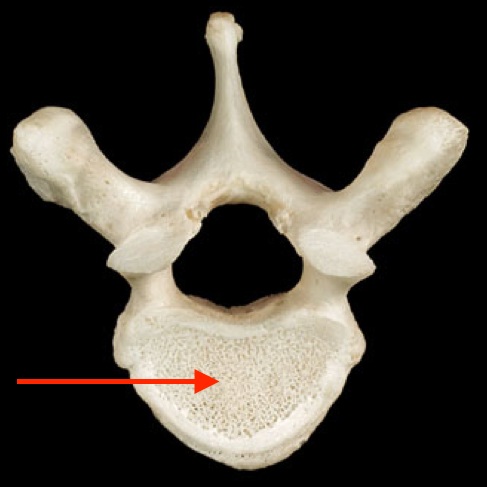

if there is a hole in the body of the vertebra for arteries what is that called

foramen vasculare